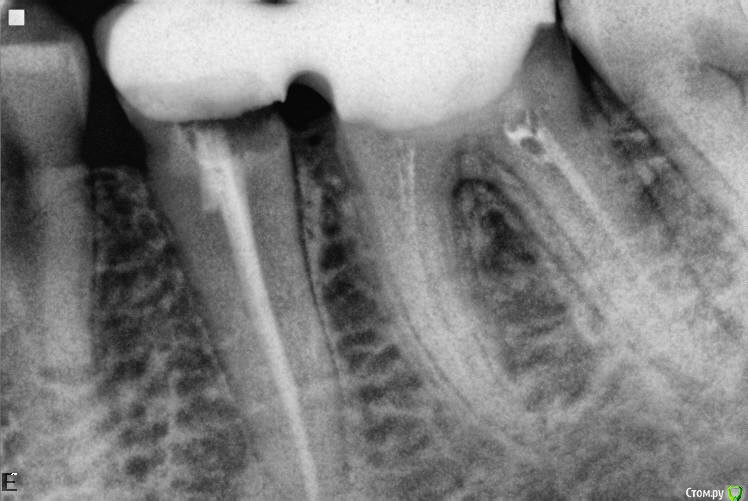

Bobon Опубликовано 13 июля, 2017 Поделиться Опубликовано 13 июля, 2017 нужно апексы нормально сфотать, не видно ничего..... Ссылка на комментарий

red_butler Опубликовано 2 августа, 2017 Поделиться Опубликовано 2 августа, 2017 Снимок после - периапикальная область обрезана. +1 покажите нормальный снимок Ссылка на комментарий